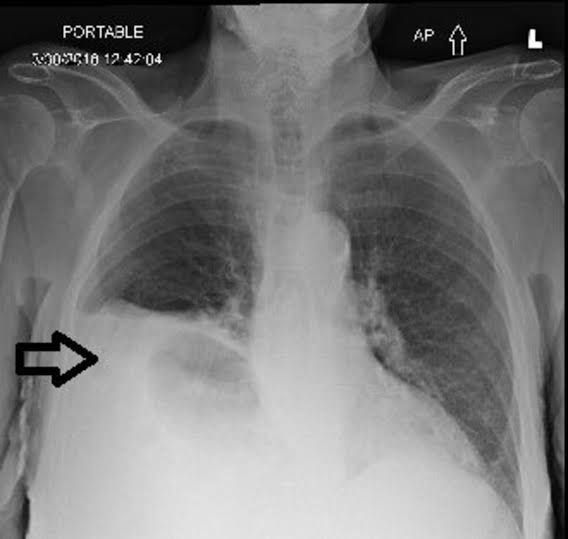

Morgagni hernias are rare congenital diaphragmatic defects that can lead to bowel obstruction and incarceration if not repaired. Surgery can be performed through either an open incision or minimally invasive techniques through the chest or the abdomen. As most of these defects are not discovered until later in childhood or adulthood, the long-term prognosis is good, with a low recurrence rate.